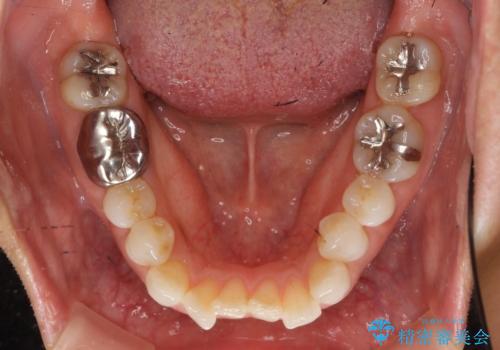

30代女性 前歯のがたつき

- 前歯のがたつきを主訴に来院。

右下の奥の銀歯も治療しています。

下の前歯を下げるため、IPR(歯をわずかに削る処置)を行っています。